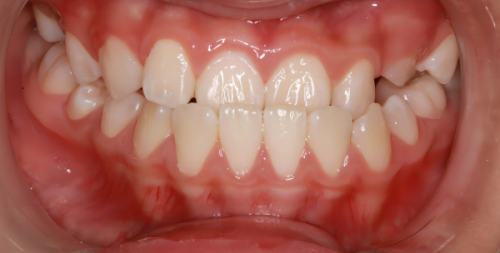

对于身体健康、没有凝血功能异常或重度妇科疾病的女性来说,普通的超声波洗牙(龈上洁治)并非完全地禁忌。超声波洗牙主要是通过高频振动去除牙齿表面的牙结石、菌斑和色素,操作过程中对牙龈的刺激相对较小,一般只会造成轻微的牙龈出血,这种程度的出血在健康女性的经期通常是可以自行止血的。不过即便如此,也需要提前评估自身的经期状态,如果经期本身就有明显的乏力、头晕等不适,还是建议暂缓洗牙。

但如果是需要进行龈下刮治这类深度洗牙项目,或者本身存在牙周炎症较重、牙龈易出血的情况,那么经期就不建议洗牙了。龈下刮治需要深入牙龈下方清理牙结石,对牙周组织的刺激更大,会导致出血量增多,而经期女性的凝血功能会有所下降,可能出现出血不止、止血时间延长的情况,还会增加感染的风险。此外,若女性本身有经期出血量大、痛经重度等问题,也应完全地避开经期洗牙。